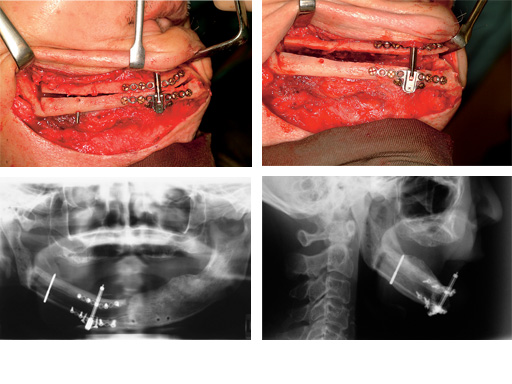

Maxillary distraction in a 34-year-old male after periodontal disease.